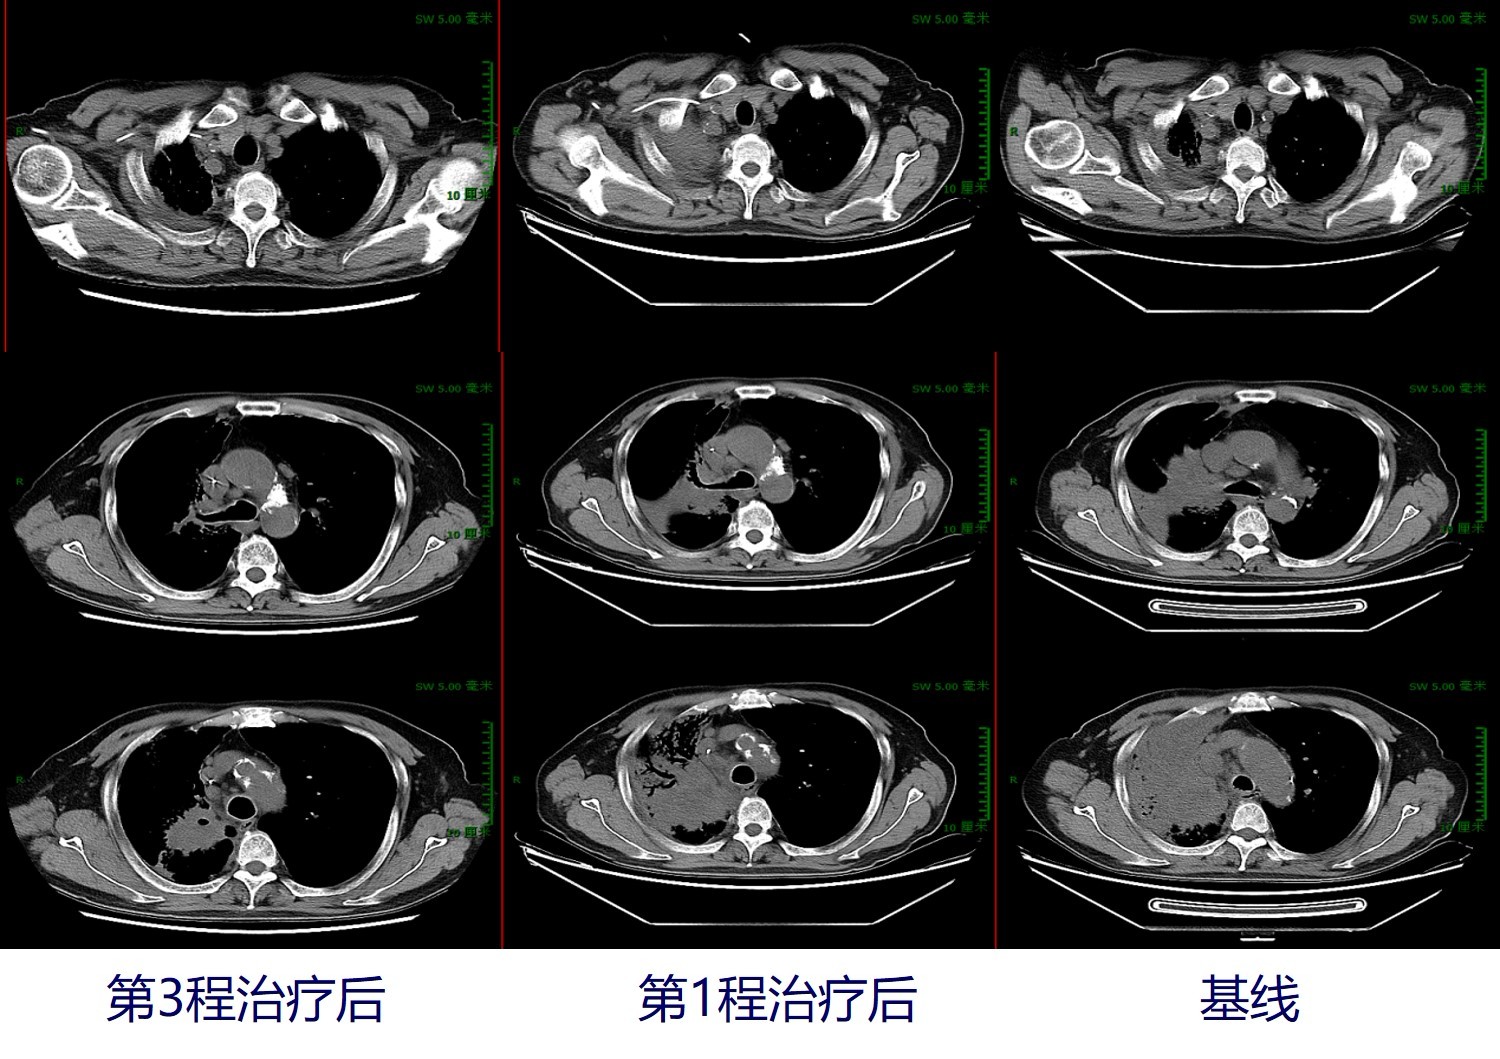

分别于2019年7月11日、2019年8月9日接受第2和第3程减量治疗,具体方案为:信迪利单抗(达伯舒)200mgd1+紫杉醇135mg/m2 d1+DDP 20mg/m2 d1-3(q21d)。治疗后副反应:化疗后不适,体重稳定,血象无异常。2019年8月31日行胸部CT检查示:右肺上叶占位(4.3cm*3.8cm)伴右肺上叶支气管截断、右肺上叶阻塞性改变,纵隔淋巴结肿大:较前(2019年7月9日)右肺上叶渗出实变有所吸收,右肺下叶斑片渗出有所吸收。头颅MRI增强:左侧额叶转移瘤(4mm),较2019年6月13日明显缩小,病灶周围水肿不明显。综合评估患者治疗后的疗效情况,外周血肿瘤标志物下降,见下图1。疗效评估显示:第1次免疫联合化疗后,疗效评价为SD;第3次免疫联合化疗后,疗效评价为PR。

图2. 治疗过程中的肺部病灶变化:肿瘤明显缩小